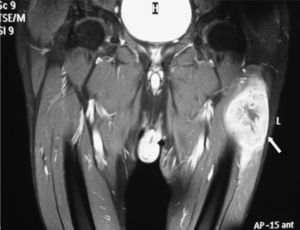

Se trata de un varón de 69 años, ex fumador, entre cuyos antecedentes personales destacaba la presencia de hipertensión arterial, dislipemia y polimialgia reumática. Consultó tras apreciar una tumoración en el muslo izquierdo de crecimiento lentamente progresivo, acompañada de un dolor sordo y continuo. Con excepción de una pérdida ponderal no cuantificada negaba otra sintomatología sistémica. Refería igualmente la aparición, al cabo de varias semanas, de una segunda lesión de menor tamaño en la pantorrilla derecha. La exploración física mostraba un paciente con buen estado general, sin hallazgos a la auscultación cardiopulmonar ni adenopatías palpables. Destacaba en la cara externa del muslo izquierdo una masa pétrea e indolora a la palpación (10×5 cm), con escasa movilidad en planos profundos, sin signos inflamatorios locales y cubierta de piel intacta, así como una segunda lesión (2×1 cm) de similares características en el gastrocnemio derecho. Una resonancia magnética (RM) con contraste puso de manifiesto una gran masa muy heterogénea de aspecto sarcomatoso en el músculo vasto externo del muslo izquierdo (fig. 1), y una masa de menor tamaño en el gastrocnemio lateral de la pierna derecha. Una citología obtenida de esta última lesión, mediante punción aspirativa con aguja fina (PAAF), fue congruente con un carcinoma pobremente diferenciado. Posteriormente, se realizó una biopsia incisional de la masa del muslo que confirmó la infiltración por un carcinoma epidermoide con fenotipo epitelial complejo en el estudio inmunohistoquímico (positividad para queratinas de alto peso molecular, panqueratinas AE1-AE3, trombomodulina, antígeno carcinoembrionario y p63). Se completó el estudio con una tomografía computarizada toracoabdominal que reveló múltiples nódulos pulmonares bilaterales indicativos de metástasis, entre los que destacaba una lesión en el vértice superior derecho de mayor tamaño (3×3,2 cm) y contornos espiculados que fue identificada como probable tumor primario. Mediante una PAAF transtorácica se obtuvo una muestra de cuyo estudio citológico fue compatible con un carcinoma escasamente diferenciado. Con el juicio de carcinoma pulmonar no microcítico (CPNM) en estadio IV, el paciente fue sometido a tratamiento quimioterápico con intención paliativa (cisplatino y docetaxel). A pesar de la disminución inicial del tamaño de las MME tras 6 ciclos de tratamiento, a los 10 meses se confirmó la progresión tumoral pulmonar, cerebral y hepática, optándose en ese momento por un manejo exclusivamente sintomático.